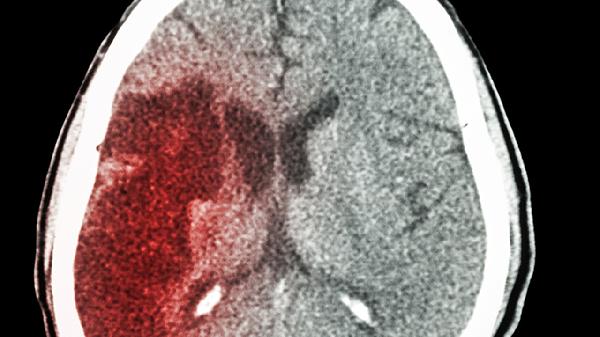

CT/MRI显示梗阻性脑积水可见梗阻点以上脑室显著扩张,如导水管梗阻时第三脑室及侧脑室膨大。交通性脑积水则表现为全脑室对称性扩大,基底池等蛛网膜下腔可能变窄或消失。